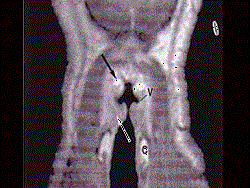

问题 男,16岁,咽异物感6年,无咽部出血及吞咽障碍。检查:舌根部中央有半球形肿物隆起,粘膜光滑,质地中等。颈部淋巴结不大: MRI检查结果如下图,下一步最重要的检查是 ( )

选项 A、针吸活检 B、纤维喉镜 C、颈部CT D、放射性I扫描 E、颈部彩超

答案 D

解析 D